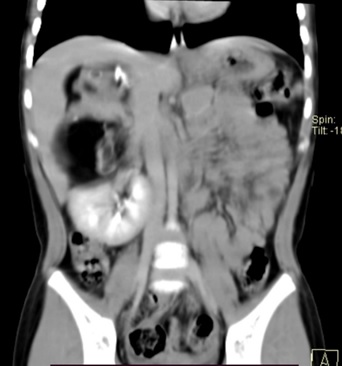

Se le realizó tomografía de abdomen contrastado donde se ubicó, en topografía suprarrenal derecha, masa de 9 x 6 x 6 cm heterogénea, de predominio hipodensa, con areas de densidad de tejidos blandos y quísticos en su interior, así como calcificaciones gruesas, que condiciona desplazamiento superior y anterior del hígado alcanzando región subdiafragmática y desplazamiento caudal del riñón derecho y su hilio vascular, además, la vena cava se desplazaba hacia la izquierda. Se observaba una interfase entre la masa y el hígado y riñón. Los hallazgos descritos eran compatibles con un teratoma (Ver figura 1). Se complementó abordaje con tomografía de torax contrastada, que no mostró evidencia de enfermedad diseminada.

Figura 1. Corte coronal en tomografía computada.

Corte coronal en tomografía computada de abdomen con contraste intravenoso que muestra una tumoración en topografía suprarrenal derecha, heterogénea, con areas de densidad de tejidos blandos y quísticos, así como calcificaciones, que desplazan estructuras adyacentes.

El estudio solicitado habitualmente por el médico de primer contacto es el ultrasonido, que permite distinguir entre componentes quísticos o sólidos, sin embargo, la tomografía o resonancia magnética son más útiles, en el sentido de que describen con mayor precisión la extensión de la lesión y su relación con las estructuras adyacentes, algo que es de gran ayuda para la planeación quirúrgica (1,5,9,10). Las calcificaciones y el desplazamiento de estructuras circundantes son hallazgos que se han descrito con frecuencia en teratomas benignos. Por otra parte, areas de hemorragia o necrosis en una masa sólida, así como la invasión a estructuras adyacentes son datos que sugieren malignidad (10,13). En nuestro caso, estaban presentes calcificaciones y desplazamiento de estructuras adyacentes. Los TRP son generalmente grandes masas que hasta en el 60 % miden ≥ 10 cm (5,8,10) en este caso medía 12 x 7 x 6 cm.